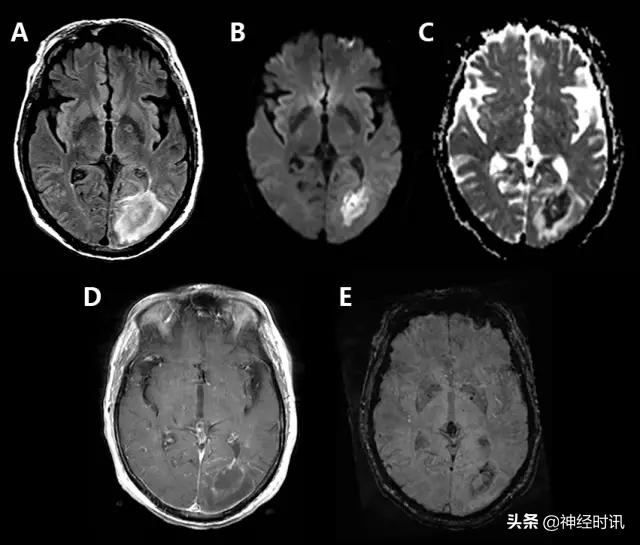

脑肿瘤

原发性脑肿瘤可以表现为急性神经功能缺损。有时低级别胶质瘤伴轻度水肿效应和皮层受累可能会与亚急性脑梗死混淆(图3),通过无血管分布、无明显弥散受限和脑沟强化,较易与其鉴别。但是,亚急性梗死伴出血和高级别出血性胶质瘤可表现为局部弥散受限、不同程度强化和占位效应,有时难以鉴别。

图3 一例49岁女性,突然醒来出现言语不清。最初CT报告左侧MCA区域脑梗死伴左侧MCA高密度(A),MRI显示非强化(B)、T2-FLAIR高信号(C)的膨胀性病灶伴弥散增加(D-DWI,E-ADC)。活检显示为间变性少突胶质细胞瘤。